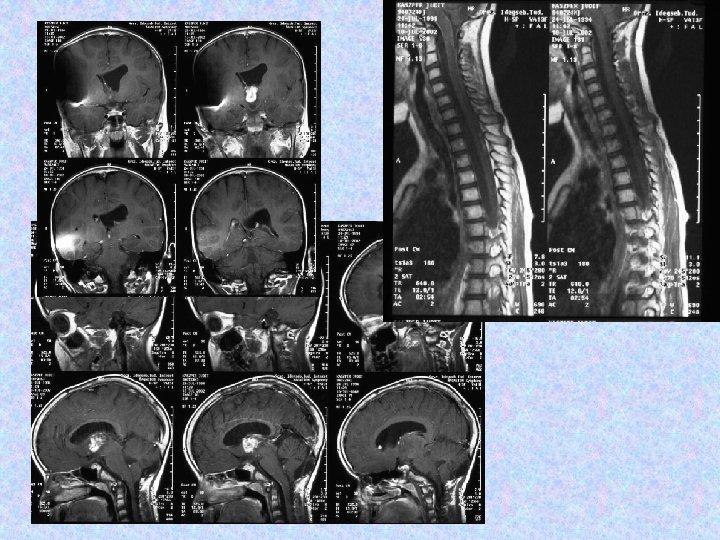

• 2000. december 4. !!! MRI majdnem teljes intracerebrális és teljes spinális regressziót mutat. !!!

• 2002. július 10 -én koponya és teljes gerinc MRI felvétel történt. A koponya MRI felvételek összevetve a 2001. június 27 -i felvételekkel aszimmetrikus kamrarendszert mutattak, a bal kamra kitágulásával. A jobb kamra szűk, a shunt vége a frontális szarv dorzális részében helyezkedik el, jól működik. A harmadik kamra területén egy intenzíven halmozó terime látható, továbbá bal kamraszarvban bazálisan. A szubarachnoideális liquorterek megtartottak, kóros halmozás nem figyelhető meg. • A gerinc MR felvételen a kraniocervikális átmenetben, a nyúltvelő ventrális felszínén sáv alakú halmozást írtak le. Th. VII-VIII. , L. I-II. csigolyákban, a conus körül szolid halmozás figyelhető meg. Az alacsonyabb thoracalis szakaszokon lévő myelon felszínén és intradurálisan homogén halmozást írtak le. • A neuro-onkológiai konzílium nem javasolt további kemo- és radioterápiát.

• A 2002. decemberi MRI felvételeken további progresszió figyelhető meg, a harmadik kamra területén és a bal kamraszarvban tumor igazolódott. Műtétet javasoltak, a szülők nem egyeztek bele, alternatív kezelést választottak. • A 2003. májusi és októberi MRI kontroll felvételek a harmadik kamrai tumor progresszióját és következményes, aszimmetrikus hydrocephalust mutattak. Műtét történt. Nem volt újabb neurológiai eltérés státuszában.